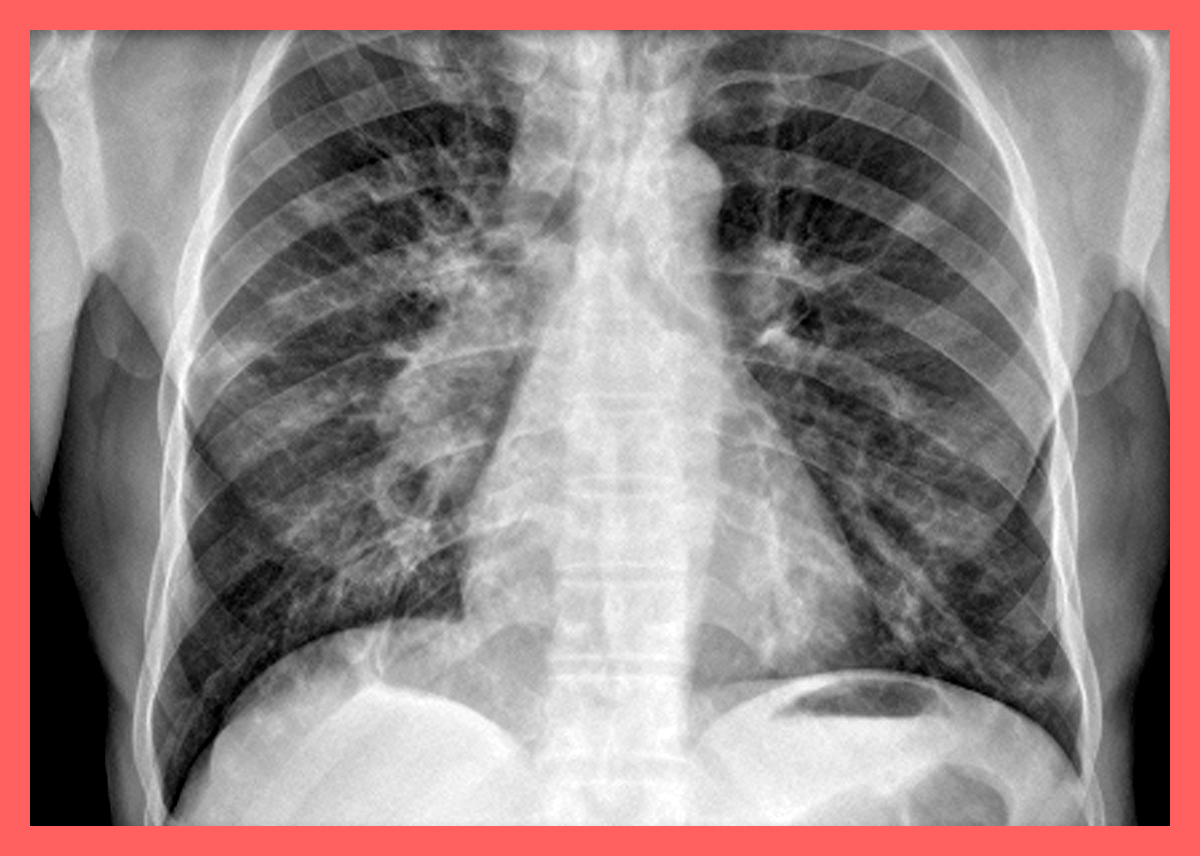

결핵 감염이 의심된다면 항산균 도말 검사를 받아야 한다. 흉부 X선 검사에서 폐결핵 의심 소견을 받았거나 기침, 가래, 발열 등의 호흡기 질환 증상이 2~3주 이상 지속되면 결핵 감염을 의심해 봐야 합니다.